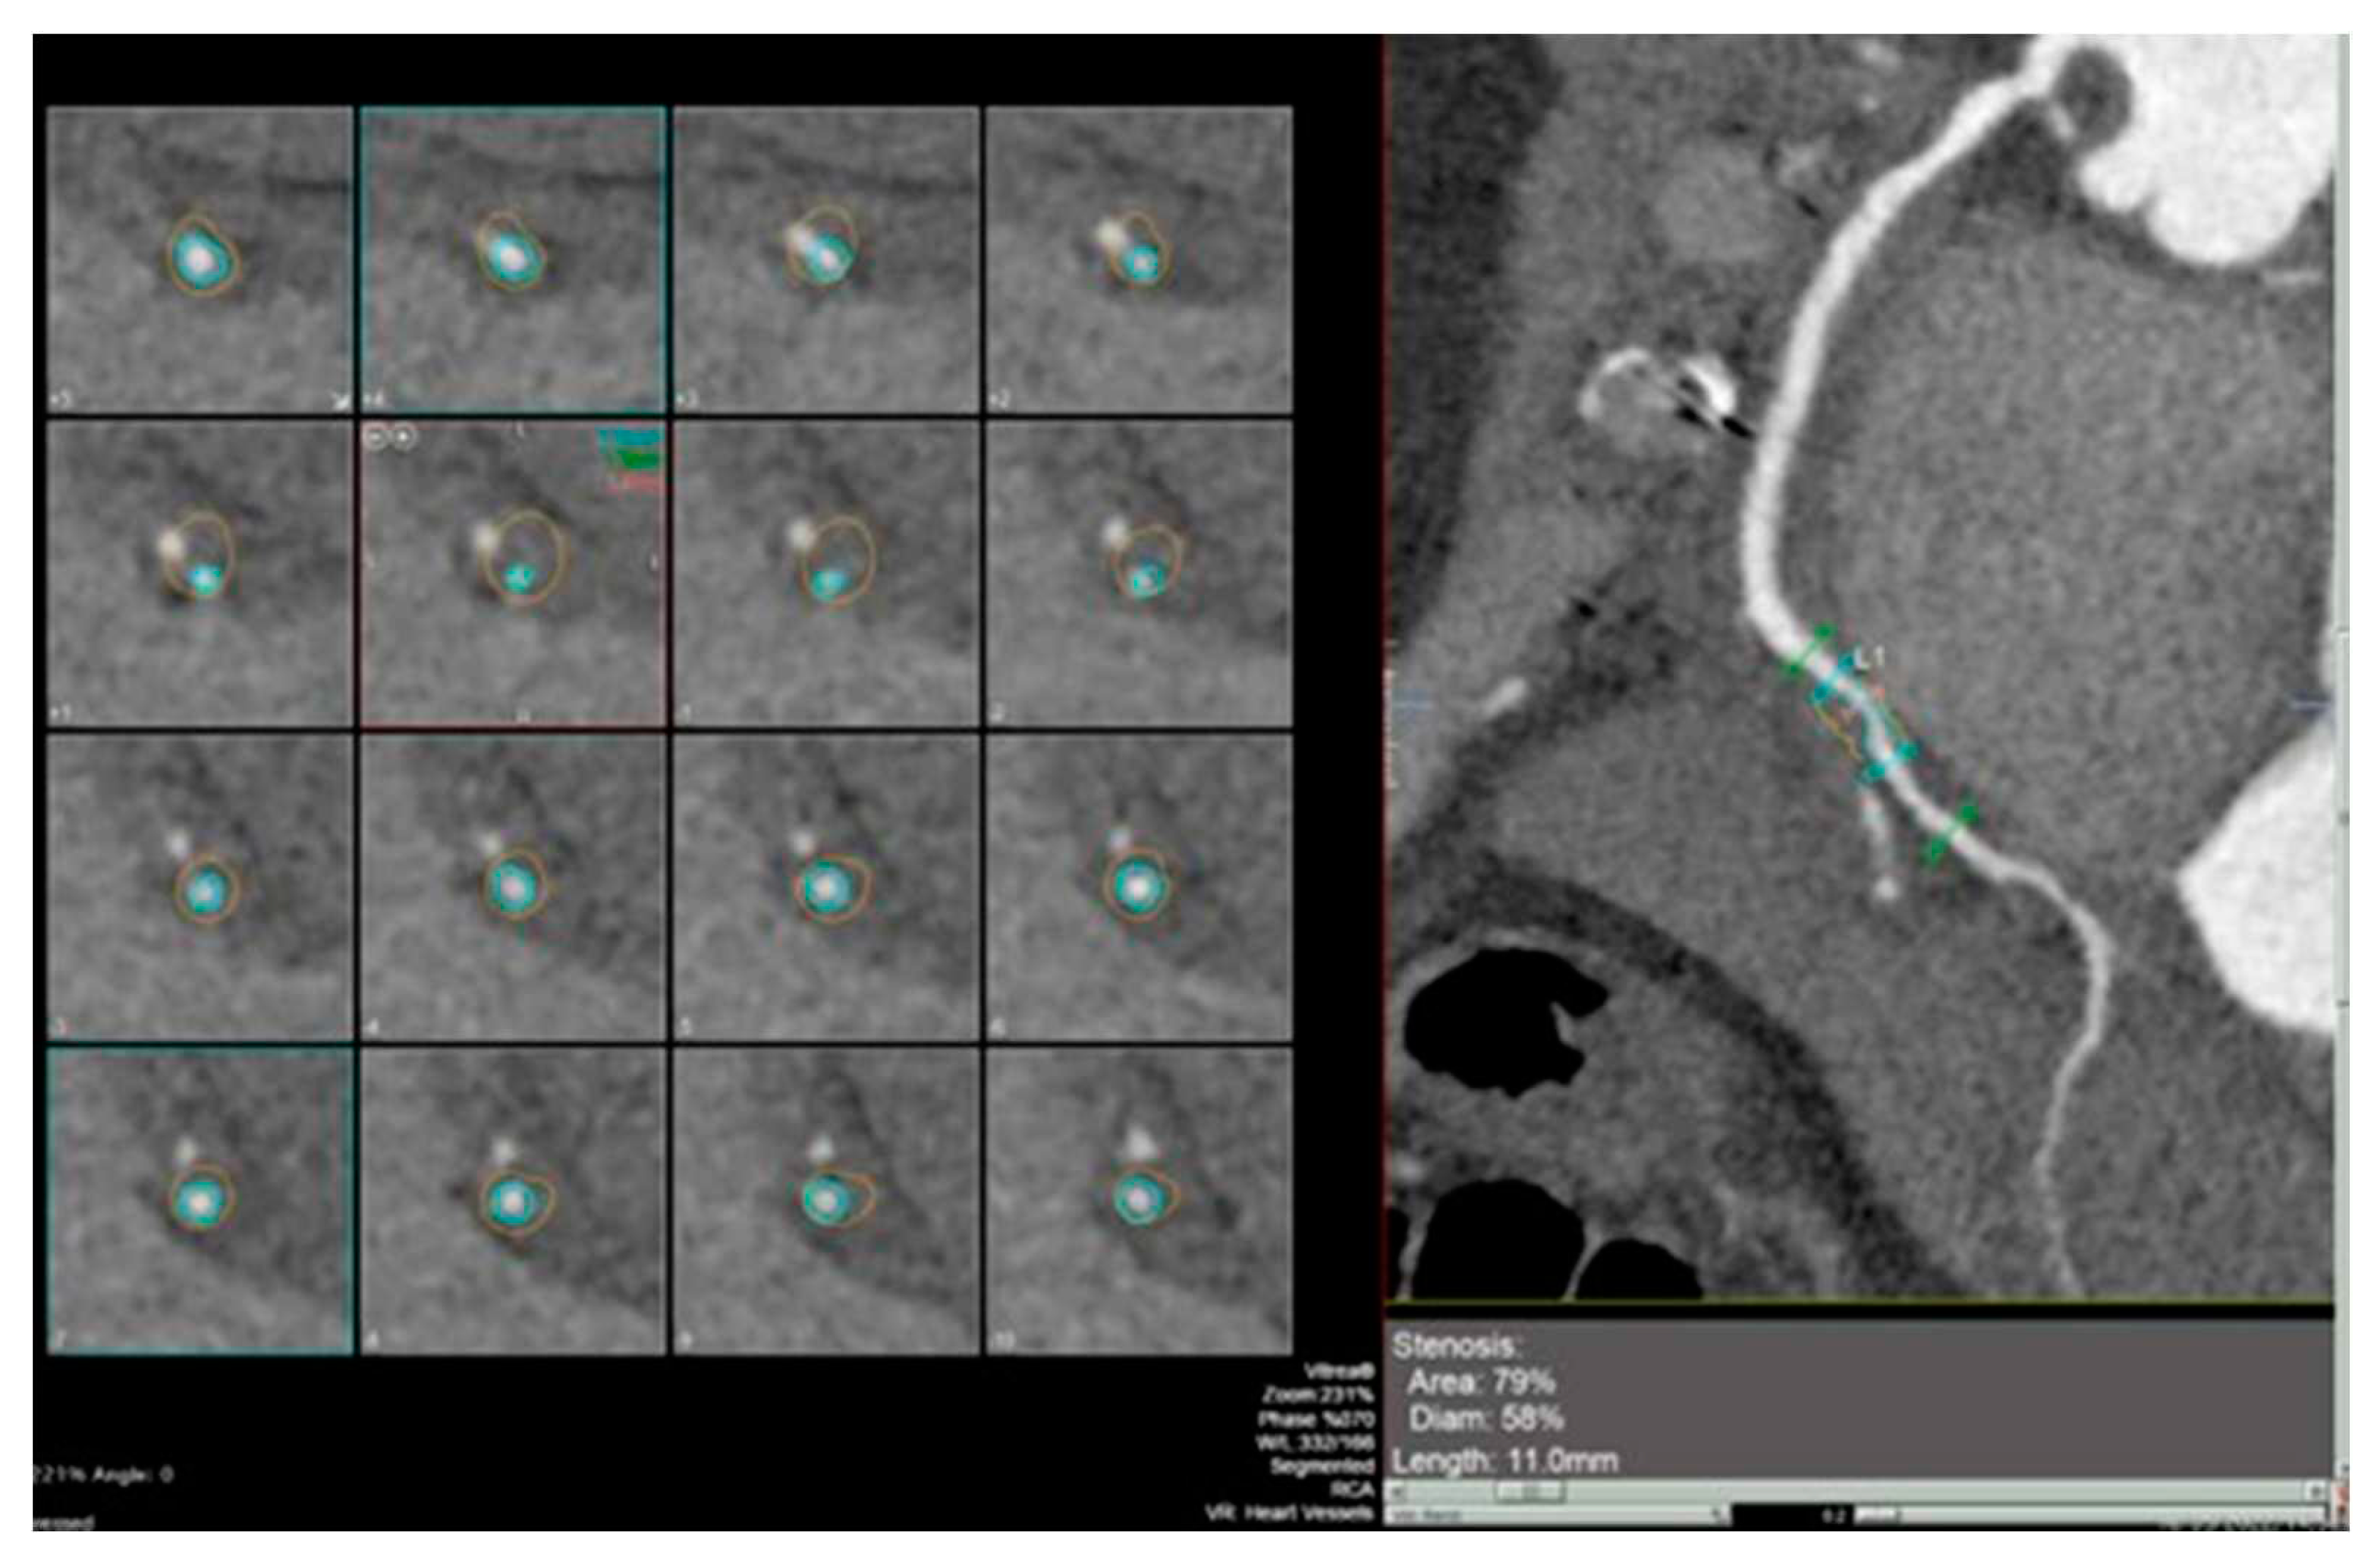

Advanced strain echocardiography can be employed to evaluate atrial function in HT recipients. Bech-Hanssen et al. [21] demonstrated a significant reduction in atrial reservoir function, assessed using speckle tracking, in HT recipients due to elevated pulmonary capillary wedge pressure (PCWP) and LA enlargement in the LA, as well as impaired longitudinal RV function in the RA. The reduction in atrial reservoir function is most pronounced in the presence of elevated filling pressures [22]. Zhu et al. observed alterations in LA function throughout all phases of the cardiac cycle, independent of the surgical technique employed. Peak LA strain was found to be associated with worse left ventricular systolic function, suggesting the potential importance of LA function in HT patients [20] [Figure 1].

Figure 1. Atrial strain in four chamber view (upper image) and in two chamber view (lower photo) assessed by transthoracic echocardiography through speckle tracking methodology.